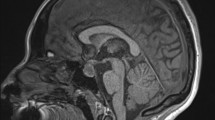

An important but often overlooked aspect of PA is that the resulting mass effect is largely due to blood and edematous, necrotic tissue, which regress over time. Prior reports have noted regression in 70–95% of patients 3 months post apoplexy (see Fig. 1) [4, 19, 61]. Thus, symptom resolution due to diminished mass effect may be noted in most patients with PA, regardless of whether they undergo surgery. Whether these studies, often performed at centers with expert pituitary teams, represent general outcomes remains to be seen, particularly since growing evidence suggests that the degree of an institution’s experience in pituitary surgery is associated with overall outcomes [4, 65,66,67]. Despite the uncertainty in current literature, immediate decompression is generally safe and commonly used as the primary treatment modality in cases of severe visual deficits [68].

Change in Volume of Apoplectic Tissue in Medically Managed Patients by 2 to 3 Months After Symptom Onset. Volumes were measured using the (A × B × C)/2 approximation method. Each line represents one patient (n = 24). There was a significant 61% median reduction in volume over time (P = .0002), with only one patient showing volume enlargement. Reproduced with permission from: Mamelak, A. et al. (2023). A Prospective, Multicenter, Observational Study of Surgical vs. Nonsurgical Management for Pituitary Apoplexy. Journal of Clinical Endocrinology & Metabolism, 109(2), e711–e725. https://doi.org/10.1210/clinem/dgad541